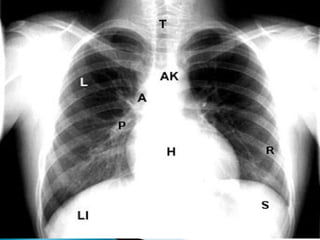

Alinhamento / Centralização

 Para que o exame esteja bem centrado, as bordas

mediais das clavículas devem estar eqüidistantes do

centro da coluna, ou seja, os processos espinhosos

devem ser vistos no meio destas extremidades e as

escápulas devem estar fora do campo.